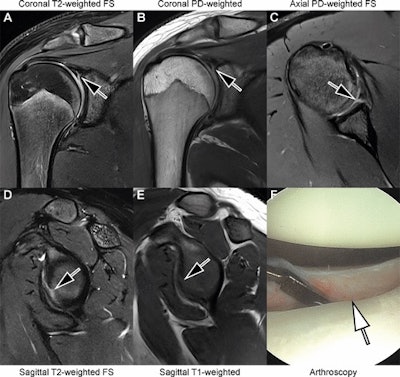

Images in an 18-year-old man with recurrent dislocations of the right shoulder. (A, B) Unenhanced coronal, (C) axial, and (D, E) sagittal deep learning super-resolution threefold parallel imaging -- accelerated turbo spin-echo MRI scans were obtained at 3-tesla field strength. (A) Coronal T2-weighted fat-suppressed (FS) and (B) coronal proton density (PD)-weighted MRI scans show a nondisplaced superior labral tear (arrows). (C) Axial proton density-weighted fat-suppressed, (D) sagittal T2-weighted fat-suppressed, and (E) sagittal T1-weighted MRI scans show continuation into a nondisplaced anteroinferior labral tear (arrows). All seven readers correctly diagnosed the arthroscopy-validated findings. (F) An arthroscopic photograph shows the anteroinferior labral tear (arrow). Image and caption courtesy of the RSNA.